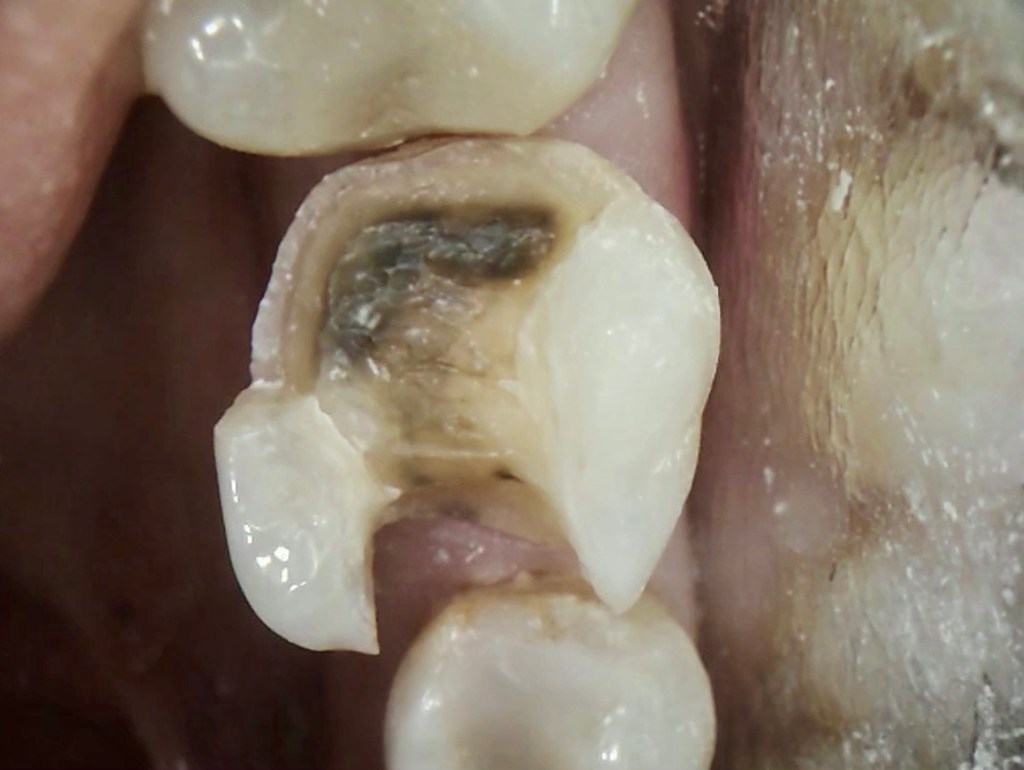

Cavity Broken Metal Filling